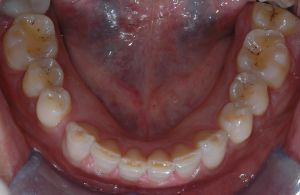

A particularly instructive example of information scale change is provided by clinical observation of the masticatory system, analyzed at progressively finer levels of resolution.

Clinical observation of occlusal–masticatory state

The clinician evaluates functional coordination, apparent efficiency of the gesture, and the presence of adaptations and compensations.

At this scale the system often appears stable and coherent, even in the presence of underlying alterations. High integration of information makes observation robust and poorly sensitive to local fluctuations. In this case, objective analysis of occlusal status is low-resolution but offers a broad view of the functional contour. In Figure 1, dental wear due to bruxism is evident and classification of the subject as a bruxer appears straightforward.